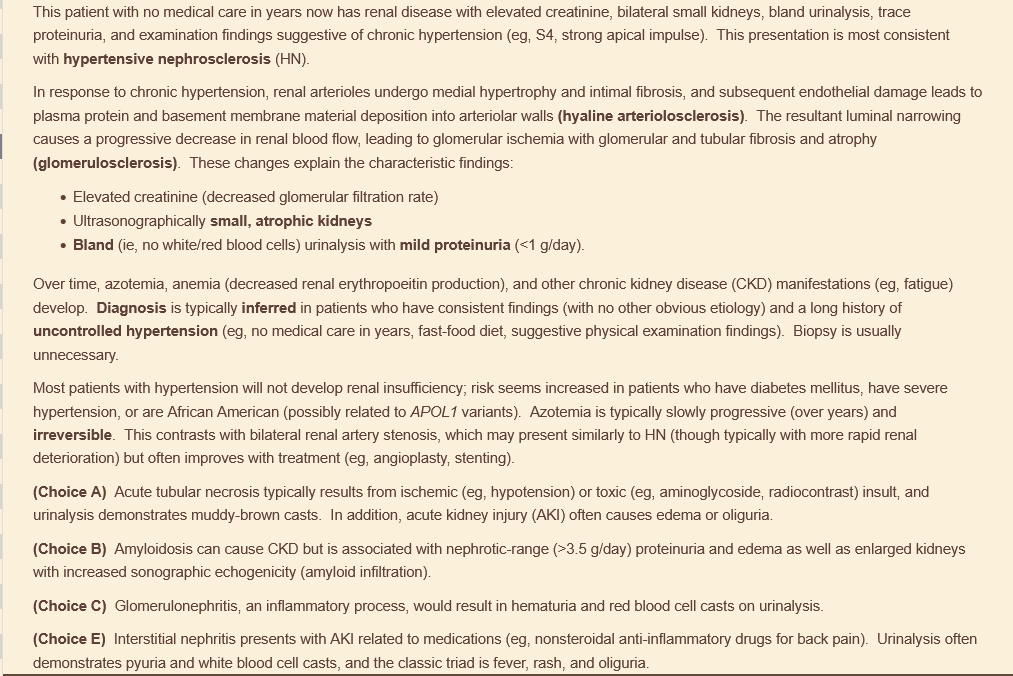

70M here for fatigue. hasnt seen a doctor in 20 years. eats lots of fast food and takes otc pain meds for intermittent back pain. urinalysis with trace protein, no casts. s4 and strong apical impulse on exam. US of abdomen reveals bilateral small kidneys

hypertensive nephrosclerosis